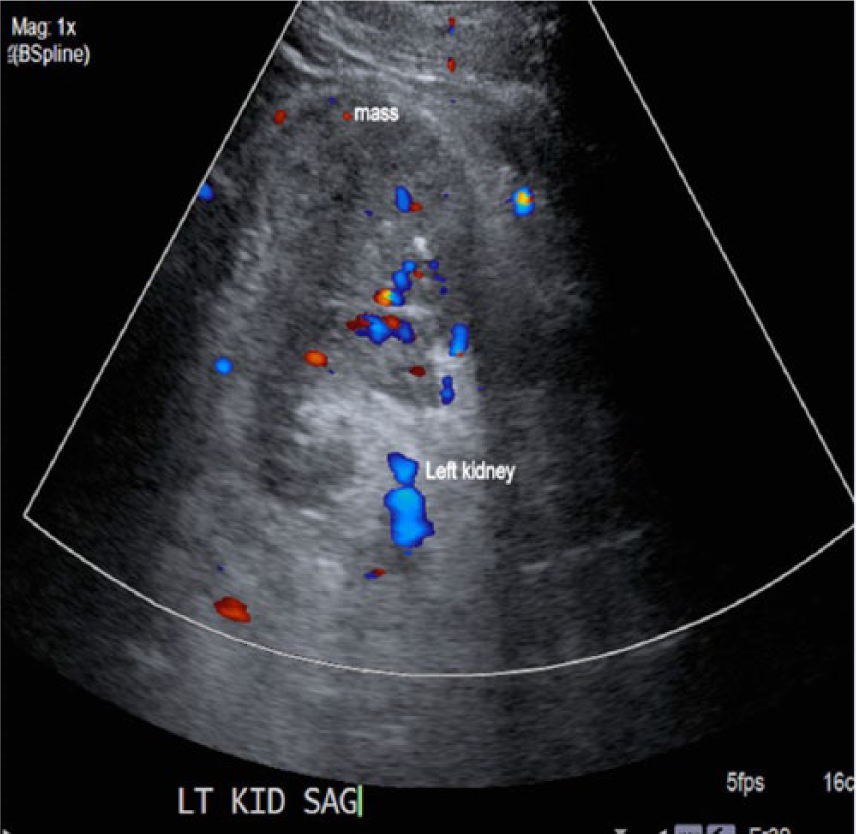

An elderly man in his early seventies was referred to the hospital as an outpatient to undergo an abdominal aortic aneurysm (AAA) screening. The patient had a history of smoking for 20 years. The sonographic examination was performed on an Acuson 2000 ultrasound system (Siemens, Washington, DC), with a curved array C5-2 probe (2-5 MHZ bandwidth). Sonographic findings showed no evidence of an AAA. Velocities and Doppler waveforms throughout the abdominal aorta were normal and showed no significant stenosis. During the examination, the sonographer observed echogenic material in the area of the inferior vena cava (IVC). Upon further examination, the IVC appeared to be thrombosed (Figures 1 and 2). Color Doppler imaging was used to confirm that the IVC was partially obstructed (Figure 3). A transverse view of the IVC and aorta also showed a thrombus in the left renal vein (Figure 4). This prompted the sonographer to extend the examination to the left kidney where a partially exophytic mass located on the anterior/superior portion of the left kidney was seen (Figures 5 and 6). The mass measured 5.43 cm long, 5.31 cm wide, and 4.30 cm anterior-posterior (AP) dimension. Color Doppler imaging showed significant vascularity within the mass (Figure 6). The findings were suspicious for renal cell carcinoma, and the patient shortly thereafter had additional testing with a computed tomography (CT) scan of the abdomen and pelvis with contrast. The CT scan confirmed a mass in the left kidney with direct tumor extension into the left renal vein. A thrombus was seen in the IVC both above and below the level of the renal veins. However, it could not be determined by imaging if the thrombus was related to bland thrombus rather than tumor thrombus. Also noted in the CT findings were prominent venous collaterals in the retroperitoneal region centrally and on the left. The patient had a complete left nephrectomy, and the placement of an IVC filter was also performed. The pathology report confirmed a 6.0 cm multifocal renal cell carcinoma with a large tumor extension into the left renal vein. The tissue histology using a hematoxylin and eosin stain showed a Fuhrman Grade 3 tumor, and the cancer was noted to be of a conventional clear cell type, which is the most common.

Longitudinal color Doppler image of the left kidney, which shows significant flow within the mass.